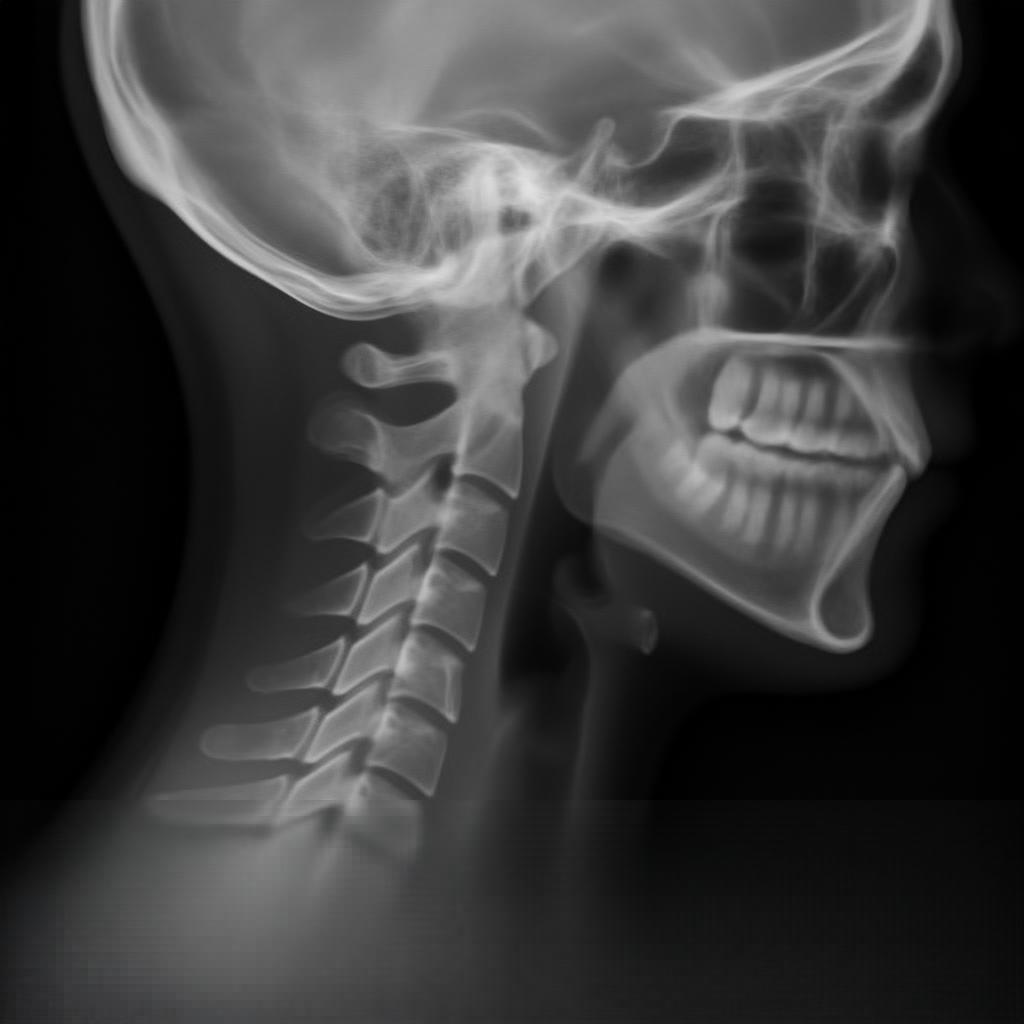

🧠 ¿Qué muestra una radiografía de columna cervical AP y LAT?

- Las vértebras cervicales: C1 (atlas) y C2 (axis) son las más especiales, y C3 a C7 tienen forma más típica.

- Discos intervertebrales: espacios entre las vértebras que pueden mostrar desgaste o hernias.

- Curvatura cervical: normalmente tiene una curva hacia adelante (lordosis).

- Articulaciones y alineación: se observa si hay desplazamientos, fracturas o malformaciones.

- Tejidos blandos: aunque no se ven con detalle, se puede inferir inflamación o masas.